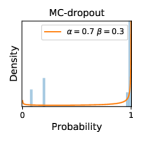

5.1 Distribution of Uncertainty Scores

Distribution of Uncertainty Scores Across Different Severity Levels As explained in Section 3, each uncertainty metric essentially defines an order/ranking among the data points. We conducted an analysis to better understand what data will be assigned high uncertainty under a particular uncertainty metric . Picking out the highest ranked data points (), we calculated the ratio of data points from each SL. Figure 4 summarizes the results as box plots for the Kaggle-DR and the Messidor-2 datasets; additional detailed statistics can be found in Table S.1 in the supplementary materials. From the plot and table, SL1 & SL2 examples account for a higher proportion among the top-ranked uncertain examples across the three ensemble methods. This finding matches our intuition that incipient disease examples (SL1 & SL2) are more likely to be considered uncertain by ensemble methods due to their ambiguity.

Comparing the three ensemble methods in Figure 4, the stacking ensemble method has the highest ratios of SL1 & SL2 data among the high-uncertainty examples it identified under both mean and var. TTA showed slightly better performance than MC-dropout but still falls behind the stacking ensemble method. Considering the fact that SL0 examples accounted for the majority of the dataset, the stacking ensemble method was much more precise (specific) in selecting truly ambiguous data points that were difficult to classify. From Figure 3, we can also see that the stacking ensemble method greatly outperformed the other two methods in finding false negatives under both mean and var uncertainty metrics.

In contrast, the MC-dropout method showed the worst overall performance among the three, as it can be seen from the high ratios of SL0 examples among the uncertain negatives in Figure 4. The histograms in Figure 2 provides another perspective to look into the phenomenon, where a decent proportion of MC-dropout model’s predictions on SL0 inputs entailed low confidence (far from 0 or 1), which from another angle explained why MC-dropout was less specific in terms of lower FNP; many no-DR inputs (i.e. SL0) were erroneously assigned high uncertainty by MC-dropout models.

It is still an open question why the evaluated MC-dropout networks signaled relatively high uncertainty on SL0 & SL3 & SL4 data that are less likely to be ambiguous. We conjecture that much of the “uncertainty” indicated by disagreement among test-time dropout samples actually reflects the stochastic nature of dropout networks rather than the real decision uncertainty associated with the data. It is worth noting that the MC-dropout model we evaluated was not weak per se; they all achieved above Area Under Curve (AUC) scores on test sets. The weakness of individual test-time samples (which explains their low-confidence predictions on SL0 & SL3 & SL4) might have been hidden when they are aggregated into an ensemble—a well-known advantage of ensemble learning. Our results suggested that the uncertainty information given by implicit ensemble methods such as MC-dropout and TTA might not be as reliable as that from explicit ensemble approaches (e.g., stacking ensembles). Similar findings on MC-dropout can be found in some previous papers [1].